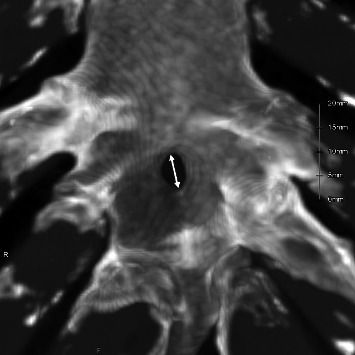

Results: Sternal foramina were present in 3.7% of adults. They were more frequent in males (4.3%) than in females (2.5%), although the difference was insignificant. Most foramina were located at the level of the fifth costal notch and overlaid the pericardium or lung in 72% of evaluable cases. The median diameter was 4.5 mm. In pediatric cases, 11 (12%) exhibited lower-sternebral ossification-center patterns that could form sternal foramina, supporting a developmental origin. An estimated 31% of these patterns may persist into adulthood with unfused segments.

Conclusion: Sternal foramina occurred in 3.7% of adults and were often situated over vital structures, posing procedural risks. Among pediatrics, ossification patterns that may impede fusion-defined as horizontal two-center or ≥ 3 center configurations-were present in 12%, and approximately 31% of these patterns appear to persist into adulthood as sternal foramina. These findings support a developmental basis for sternal foramina and emphasize the importance of recognizing them during imaging and procedural planning.